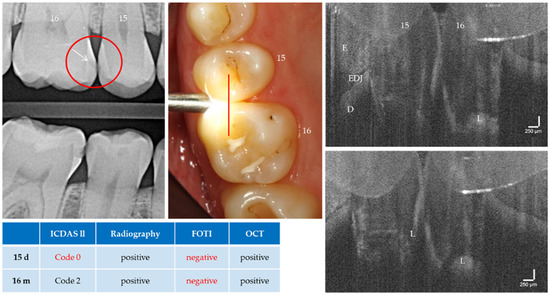

Caries, the world’s most common chronic disease, remains a major cause of invasive restorative dental treatment. To take advantage of the diagnostic potential of optical coherence tomography (OCT) in contemporary dental prevention and treatment, an intraorally applicable spectral-domain OCT probe has been developed based on an OCT hand-held scanner equipped with a rigid 90°-optics endoscope. The probe was verified in vitro. In vivo, all tooth surfaces could be imaged with the OCT probe, except the vestibular surfaces of third molars and the proximal surface sections of molars within a "blind spot" at a distance greater than 2.5 mm from the tooth surface. Proximal surfaces of 64 posterior teeth of four volunteers were assessed by intraoral OCT, visual-tactile inspection, bitewing radiography and fiber-optic transillumination. The agreement in detecting healthy and carious surfaces varied greatly between OCT and established methods (18.2–94.7%), whereby the established methods could always be supplemented by OCT. Direct and indirect composite and ceramic restorations with inherent imperfections and failures of the tooth-restoration bond were imaged and qualitatively evaluated. The intraoral OCT probe proved to be a powerful technological approach for the non-invasive imaging of healthy and carious hard tooth tissues and gingiva as well as tooth-colored restorations. Full article

Figure 1